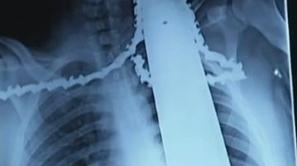

James Valentine motorna žaga nesreča

Motorka se mu je zarila v ramo in vrat

21-letni delavec se je ponesrečil z motorno žago, ki je pristala v njegovi rami in vratu.